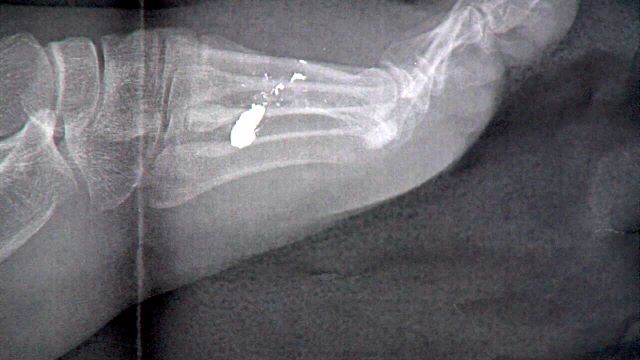

16-year-old Destiny McCubbin threw a house party she said she intended to be like the movie 'Project X.' Instead, four people, including herself, were shot. This x-ray shows the bullet in her foot.

"He hit me in the foot," she said. "My cousin was holding a cup and a bullet went through the cup."